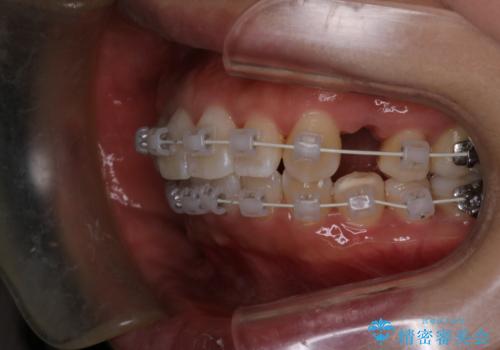

- 矯正装置

- 審美装置

- 治療期間

- 1年8ヶ月

- 治療回数

- 10-30回